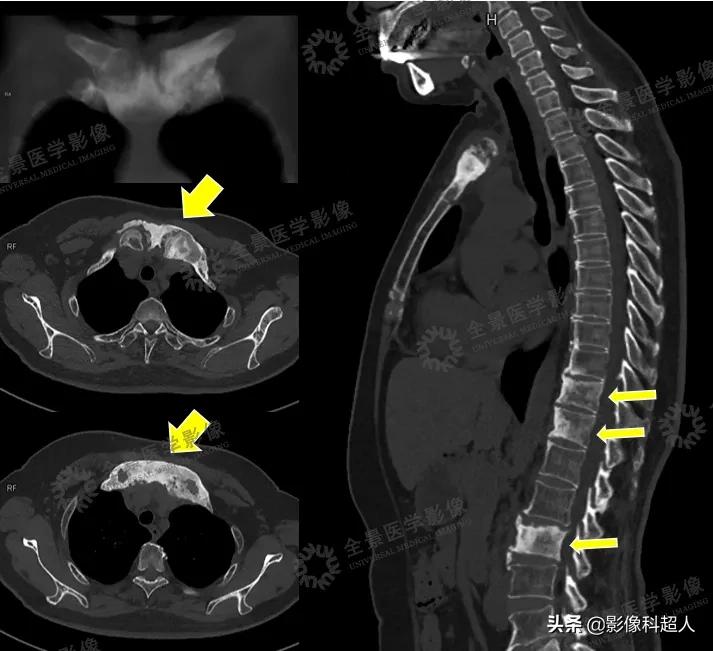

在进行初步PET/MR成像分析后,医生同时又为刘女士补充了CT扫描观察骨质情况。

CT影像资料

多模态影像可见: • 双侧锁骨头、胸骨柄骨质肥厚,密度不均匀增高,T2WI呈不均匀低信号,DWI呈不均匀高信号,右侧胸锁关节FDG轻度摄取增高,SUVmax=2.5• 胸骨体上段见局灶性FDG摄取增高,SUVmax=3.7,DWI呈高信号,ADCmin=1.401,余序列未见明确显示,骨质密度未见明显异常• T11、T12、L3、L5椎体骨质密度不均匀增高,前角为著,T2WI呈高信号,DWI呈高信号,ADCmin=0.679,FDG摄取缺失

- CT可用于评估骨质侵蚀、骨皮质肥厚、髓腔硬化等表现。